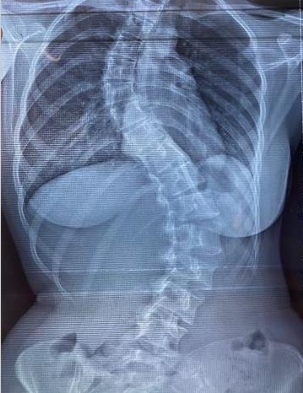

คุณ Neomii

อาการ: กระดูกสันหลังคด (Scoliosis)

"มีอาการปวดหลังเรื้อรังจากกระดูกสันหลังคด หลังมารักษาและปรับโครงสร้างที่นี่ แนวโค้งกระดูกดีขึ้นมาก อาการปวดหายไปเลยค่ะ"

★★★★★